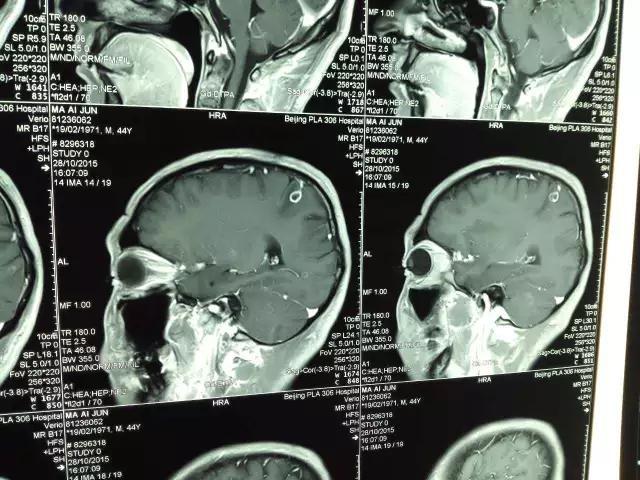

11月9日,在解放军第306医院展开了国内首例机器人辅助的立体定向脑囊虫摘除手术,患者为44岁男性,脑部MRI图像如下图,可清晰看见位于患者顶叶的囊虫。由于囊虫位于功能区,传统的开颅手术后易引发患者并发症,比如瘫痪。